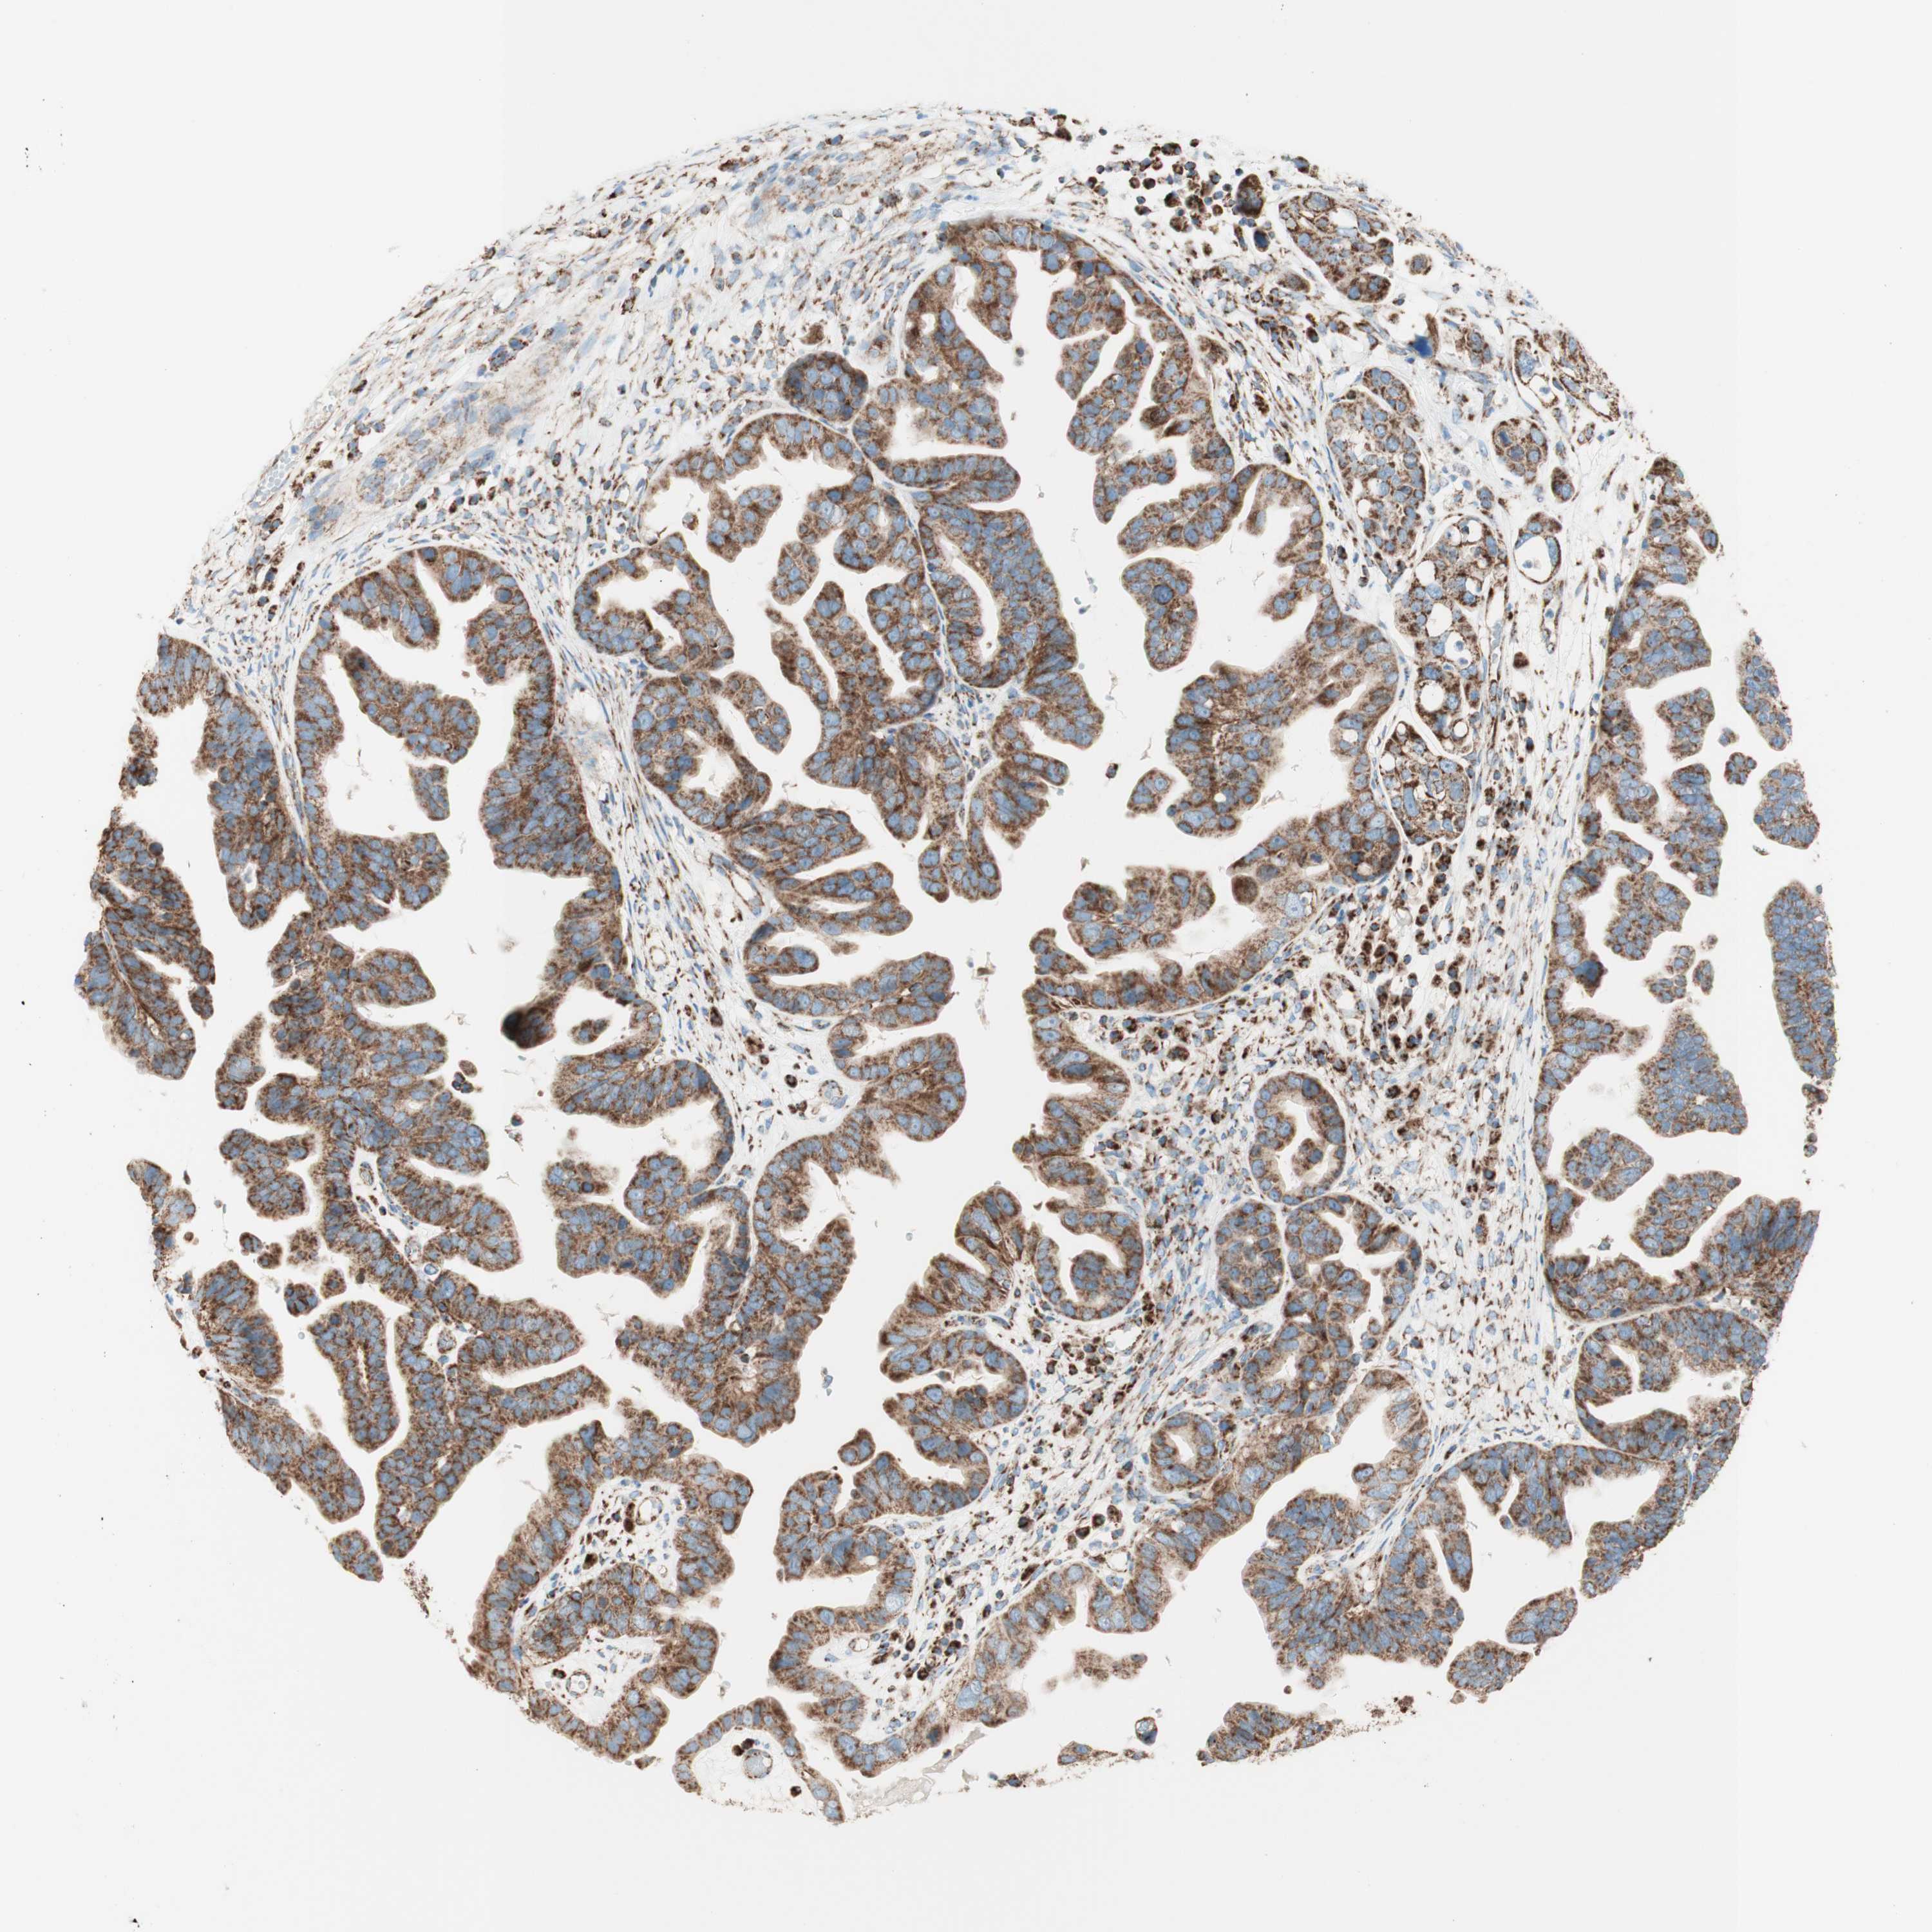

OVARIAN CANCER - Protein expressioni

A mouse-over function shows sample information and annotation data. Click on an image to view it in a full screen mode. Samples can be filtered based on level of antibody staining by selecting one or several of the following categories: high, medium, low and not detected. The assay and annotation is described here.

Note that samples used for immunohistochemistry by the Human Protein Atlas do not correspond to samples in the TCGA dataset.

Antibody stainingi

Antibody staining in the annotated cell types in the current human tissue is reported as not detected, low, medium, or high, based on conventional immunohistochemistry profiling in selected tissues. This score is based on the combination of the staining intensity and fraction of stained cells.

Each image is clickable and will lead to virtual microscopy that enables deeper exploration of all samples and also displays staining intensity scores, fraction scores and subcellular localization as well as patient and tissue information for each sample.

Antibody HPA011562

Antibody CAB005585

Staining

High

Cystadenocarcinoma, serous, NOS

Carcinoma, endometroid

Cystadenocarcinoma, mucinous, NOS

Carcinoma, NOS